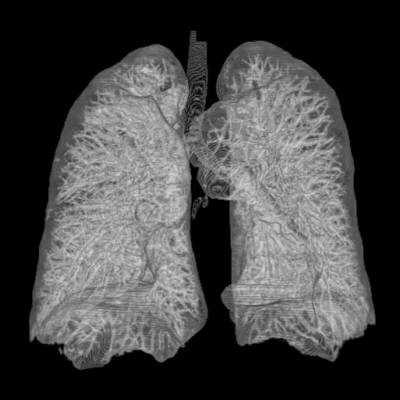

Co to jest rak płuc?

Rak płuc to jedna z najczęstszych i najgroźniejszych form nowotworów złośliwych na świecie. Charakteryzuje się niekontrolowanym wzrostem komórek w tkankach płuc, co prowadzi do powstawania guzów. Istnieją dwa główne typy raka płuc: rak płaskonabłonkowy oraz rak drobnokomórkowy, z których każdy ma swoje specyficzne cechy i różne podejścia do leczenia.

Wczesne stadia raka płuc często przebiegają bezobjawowo, co sprawia, że diagnoza jest stawiana zazwyczaj w późniejszych fazach choroby. Objawy mogą obejmować przewlekły kaszel, duszność, ból w klatce piersiowej oraz krwioplucie. W miarę postępu choroby mogą wystąpić także inne dolegliwości, takie jak utrata masy ciała czy ogólne osłabienie organizmu.

Leczenie raka płuc zależy od wielu czynników, w tym typu nowotworu, jego stadium oraz ogólnego stanu zdrowia pacjenta. Metody leczenia obejmują chirurgię, chemioterapię, radioterapię oraz terapie celowane. W ostatnich latach rozwój medycyny spowodował wzrost skuteczności niektórych terapii, co daje nadzieję na poprawę rokowań dla pacjentów.

W przypadku raka płuc, rokowanie i szanse na wyleczenie są silnie uzależnione od stadium zaawansowania choroby w momencie diagnozy. Wczesne wykrycie nowotworu znacząco zwiększa szanse na skuteczne leczenie i długoterminowe przeżycie. Niestety, wiele przypadków jest diagnozowanych w zaawansowanym stadium, co znacznie obniża szanse na całkowite wyleczenie. Statystyki wskazują, że pięcioletnie przeżycie w przypadku wczesnego stadium wynosi około 50-70%, natomiast w przypadku zaawansowanego raka płuc jest to znacznie mniej, często wynoszące zaledwie kilka procent.